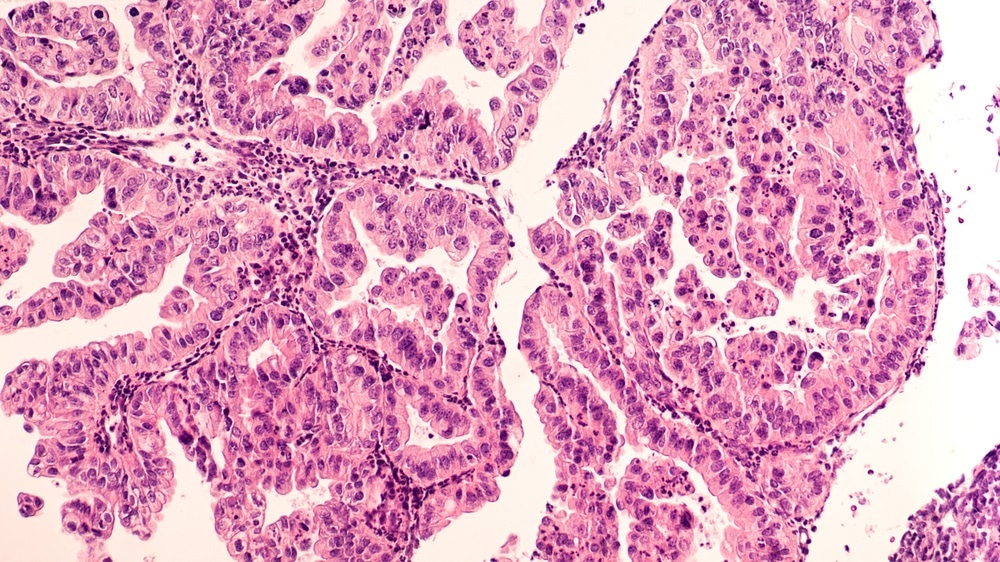

ovarian cancerImage Credits: David A. Litman / Shutterstock.com